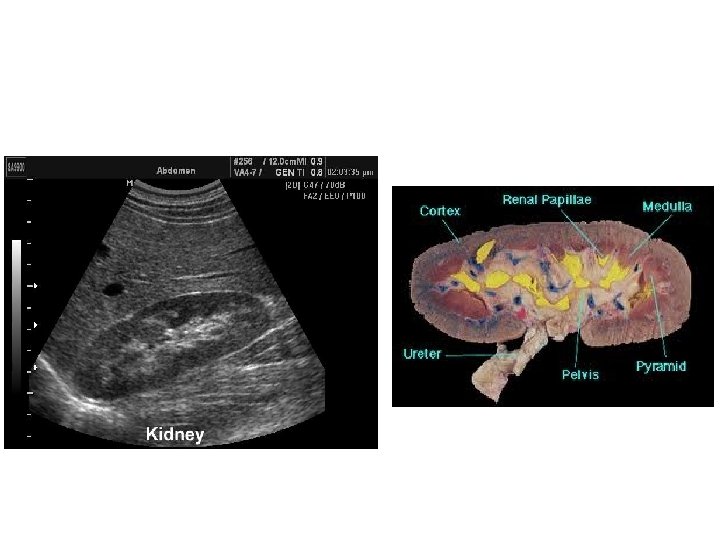

US • Use high frequency sound wave. • Contrast between tissue is determined by sound reflection.

US Image features: • • Operator dependant. Projectional image. Good resolution. Used for stone, hydronephrosis, focal lesion.